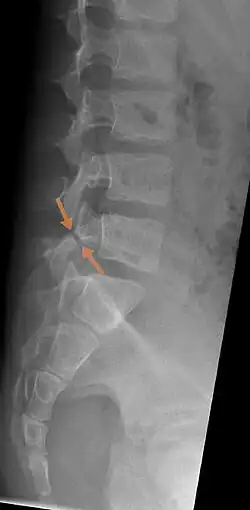

![]() | |

| Arrows show break in pars interarticularis at L5. X-Ray of lumbar spine, lateral projection, in an 11-year-old boy | |

The scottie dog sign It was once used as a diagnostic sign in x-rays, for lumbar spondylolysis, but it is not commonly in use nowadays because of the advent of more sensitive diagnostic methods such as the CT scan and MRI scan. If spondylolysis is present, the pars interarticularis, or the neck of the dog, gives the appearance of a Scottish Terrier with a collar around its neck.[7]

X-Ray

X-rays (electromagnetic radiation) are projected through the body to produce an image of its internal structures. The radiation is more attenuated (absorbed) by the denser tissues of the body (i.e. bone) than the softer tissues (i.e. muscles, organs, etc.) creating a picture composed of shades of grey ranging from white to black. A vertebra with a fracture or defect of the pars interarticularis will have a dark mark through this region of bone. Since this is difficult to see on the AP (anterior posterior) x-ray view an oblique x-ray of the lumbar spine can usually identify the spondylolysis. If inconclusive a further CT scan can produce a 3-dimensional images to more clearly show the defect although the exam increases the patients radiation dose by at least an order of magnitude than plain x-rays.[16][17]